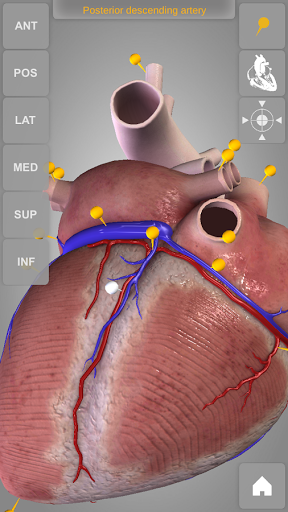

Heart 3D Atlas of Anatomy allows you to rotate a highly realistic 3D heart model as it was in your hands.

The human heart anatomical 3D model is revolvable in any direction giving a 360° view of the object.

User can choose external view or section view. Moreover, the names of specific anatomical areas can be shown touching the related pins (available in the full version only).

Heart app is part of 3D Atlas of Anatomy collection, a human anatomy reference atlas for tablet and smartphone devices. The 3D medical models in these apps are similar to classic real plastic models but with the great benefits to be always available on your portable devices when you need them and occupy no physical space.

These apps can be of great help for students of medicine or to anyone who needs to study human anatomy shape in detail and from any angle. Immediacy and simplicity together with high quality are distinctive features of the app.